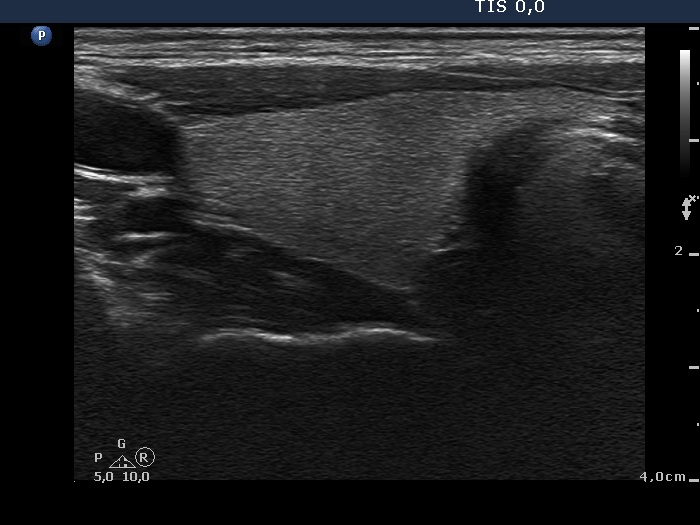

Study on 100 consecutive patients with thyroid nodule - case 031 (ultrasonographic picture 5)

Left lobe, longitudinal scan.